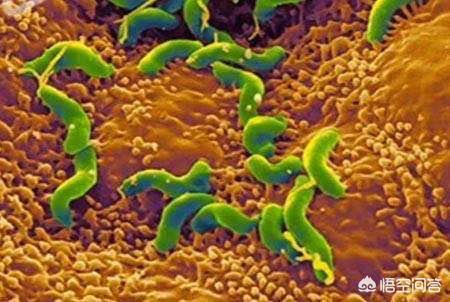

(1)口腔疾患、口腔衛生状態が悪く、う蝕、歯肉炎、歯周炎、口腔粘膜炎の患者を患っている場合、口腔内は細菌、特に嫌気性細菌が繁殖しやすく、その分解により硫化物が発生し、口臭の原因となる。

(2)消化性潰瘍、慢性胃炎、機能性ディスペプシアなどの胃腸障害が口臭を伴うことがある。原因は、口臭の原因となるヘリコバクター・ピロリ感染による硫化物の直接産生かもしれない。

(1)口腔衛生が悪く、口腔内の歯石が多く、歯茎が赤く腫れ出血しやすく、おおよそ口腔内に細菌が多く繁殖し、これらの細菌が産生された老廃物の代謝を起こし、口臭がひどくなる。

(2)口の中の歯が感染し、その空洞が掃除のしにくい食べ物で満たされ、そのような食べ物が口の中で発酵することも深刻な口臭の原因となる。